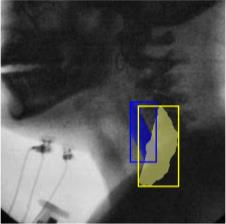

The videofluoroscopic swallowing study (VFSS) is a gold-standard imaging technique for assessing swallowing, but analysis and rating of VFSS recordings is time consuming and requires specialized training and expertise. Researchers have recently demonstrated that it is possible to automatically detect the pharyngeal phase of swallowing and to localize the bolus in VFSS recordings via computer vision, fostering the development of novel techniques for automatic VFSS analysis. However, training of algorithms to perform these tasks requires large amounts of annotated data that are seldom available. We demonstrate that the challenges of pharyngeal phase detection and bolus localization can be solved together using a single approach. We propose a deep-learning framework that jointly tackles pharyngeal phase detection and bolus localization in a weakly-supervised manner, requiring only the initial and final frames of the pharyngeal phase as ground truth annotations for the training. Our approach stems from the observation that bolus presence in the pharynx is the most prominent visual feature upon which to infer whether individual VFSS frames belong to the pharyngeal phase. We conducted extensive experiments with multiple convolutional neural networks (CNNs) on a dataset of 1245 bolus-level clips from 59 healthy subjects. We demonstrated that the pharyngeal phase can be detected with an F1-score higher than 0.9. Moreover, by processing the class activation maps of the CNNs, we were able to localize the bolus with promising results, obtaining correlations with ground truth trajectories higher than 0.9, without any manual annotations of bolus location used for training purposes. Once validated on a larger sample of participants with swallowing disorders, our framework will pave the way for the development of intelligent tools for VFSS analysis to support clinicians in swallowing assessment.